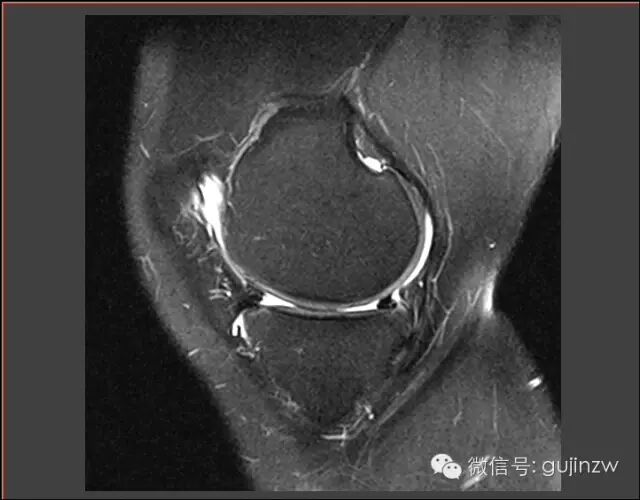

MRI

关节镜